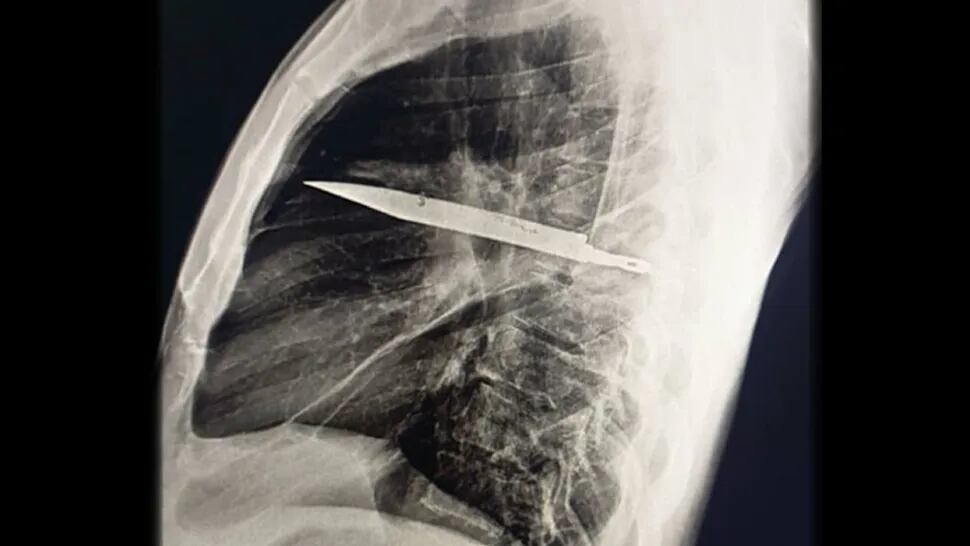

Um homem de 44 anos, da Tanzânia, descobriu que carregava uma lâmina de faca em seu peito há oito anos. O objeto foi identificado após ele procurar atendimento médico devido a secreção no peito. Exames revelaram que a lâmina estava entre as costelas, sem atingir órgãos vitais.

O paciente explicou que, em 2017, foi esfaqueado durante uma briga e recebeu apenas o atendimento médico básico. Na ocasião, não foram realizados exames de imagem e ele foi liberado após os primeiros socorros. Desde então, ele não apresentou sintomas relacionados ao ferimento.

Exames de raio-X revelaram que o corpo do paciente havia formado uma cápsula fibrosa ao redor da lâmina, o que isolou o objeto e evitou danos maiores. Após a descoberta, o paciente foi submetido a uma cirurgia para remoção da lâmina e drenagem da secreção.